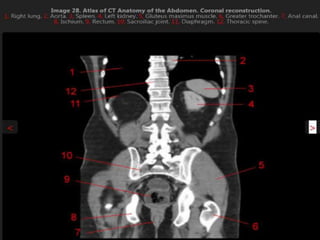

CT cross sectional anatomy.